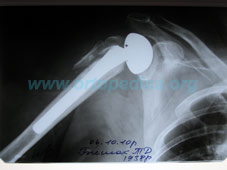

Рентгенограмма плечевого сустава после эндопротезирования